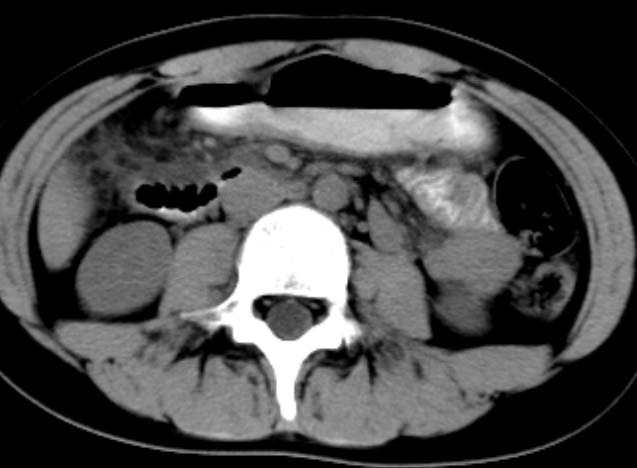

女,14岁。腹痛3天。腹部触诊未触及包块。碘剂阳性未增强。求助战友。。。。。。。。。。。

胰头部增大,周围模糊,有渗出,胰腺炎可能性大,建议结合化验检查;左侧输尿管上段略扩张.

1)急性胰腺炎。2)肝右叶后上段肝内胆管结石。3)左侧输尿管上段扩张,原因待查。

是不是胰腺炎结合几项化验指标确诊不是问题,我觉着下腹部及盆腔应观察一下。

病灶应在胰头下区,不一定是胰头,结合周边低密度水肿,是否可能为十二指肠(xi)室炎症或其它炎症。

胰周无明显渗出,吉氏筋膜未见增厚。血尿试验室检查不支持。排除胰腺炎。